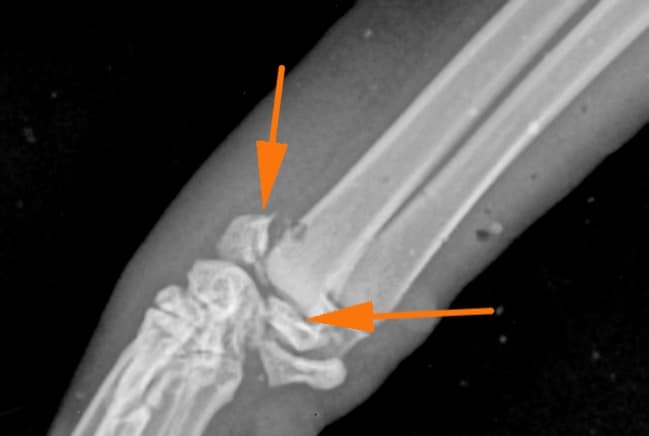

La classification de Salter-Harris des fractures du cartilage de croissance, décrite en médecine humaine donne une indication pronostique : une fracture Salter-Harris de type 1 aura un meilleur pronostic que le type 5. Toutefois, l’âge de l’animal au moment de la fracture et l’implication de l’articulation dans la fracture sont également très importants.

Parfois, une partie du cartilage reste fonctionnel et le traumatisme de celui-ci peut entrainer une croissance anormale. L’axe de l’os est modifié car une partie du cartilage de croissance va continuer à grandir mais pas l’autre. Cela peut entrainer des déformations du membre handicapantes.

Le traitement est, comme pour beaucoup de fractures chez le chat, chirurgical. Il faut alors réduire la fracture pour réaligner les abouts osseux et maintenir l’os dans sa conformation naturelle puis la stabiliser avec des implants, le plus souvent des broches qui limitent moins la croissance.

La fracture est réduite, le plus souvent avec des broches et parfois des vis. La quantité de matériel orthopédique est limitée afin de traumatiser le moins possible l’os en croissance. Des radiographies sont réalisées après l’intervention.